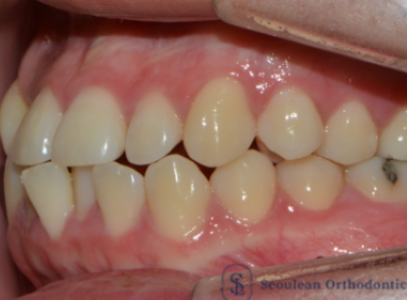

분당교정치과 / 치아 중심선이 어긋나서 고민이라면? – 실제 치료 사례